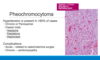

What is the 10% rule associated with Pheochromocytomas (5 of them)?

- 10% are extra-adrenal (paraganglioma)

- 10% are bilateral

- 10% in kids

- 10% are malignant

- 10% are NOT associated with HTN

The histological pattern in pheochromocytomas is composed of clusters of polygonal to spindle-shaped chromaffin or chief cells surrounded by what?

Supporting sustentacular cells, creating small nests or alveoli (zellballen) that are supplied by rich vascular network

The cytoplasm of cells within a pheochromocytoma has a finely granular appearance and is best demonstrated with what stain due to granules containing catecholamines?

What is the dominant clinical manifestation of pheochromocytomas and what is the classic triad?

- HTN which can be either chronic or paroxysmal

- Triad = Headache + Palpitations + Diaphoresis